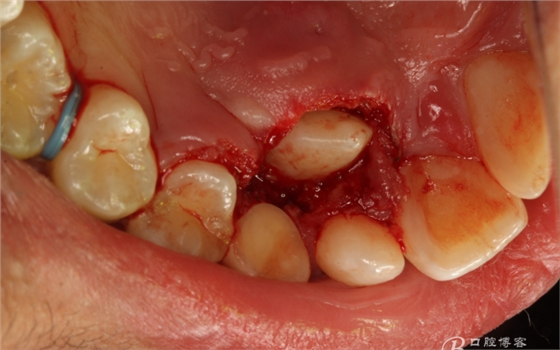

圖7.局部麻醉下、電刀切除覆蓋在13上的腭側(cè)粘膜組織。

圖8.繼續(xù)電刀切除腭側(cè)粘膜組織

圖9.清理切除部分腭側(cè)組織后的13牙冠。